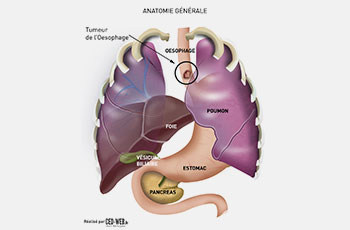

Découvrez notre collection unique d’illustrations conçues pour le domaine médical et scientifique. Chaque création combine rigueur scientifique et créativité artistique, offrant des visuels clairs et pédagogiques pour simplifier des concepts complexes.

De l’anatomie humaine aux processus biologiques, nos illustrations sont idéales pour enrichir des supports de communication, des publications académiques, des présentations professionnelles ou encore des formations en ligne.

Chaque projet est réalisé avec soin, en collaboration étroite avec des experts, afin de garantir une précision scientifique et une esthétique soignée.

Ce portfolio reflète notre passion pour la vulgarisation scientifique et notre engagement à transformer des connaissances spécialisées en outils accessibles et impactants.